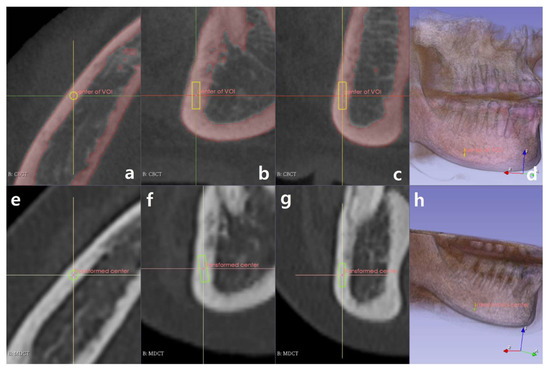

2.3. Software Development to Extract Information of the ROIs

2.4. Criteria for Selecting ROIs